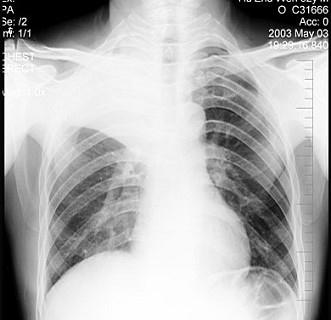

男性患者,52岁,体检胸片如图,最明确的是 ( )A.右上肺不张B.胸膜肥厚C.包裹性积液D.炎症E.支气管扩张

问题 男性患者,52岁,体检胸片如图,最明确的是 ( )

选项 A.右上肺不张 B.胸膜肥厚 C.包裹性积液 D.炎症 E.支气管扩张

答案 A